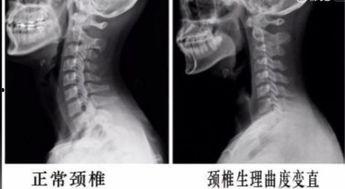

颈椎曲度变直锻炼视频,跟随视频轻松恢复健康曲线